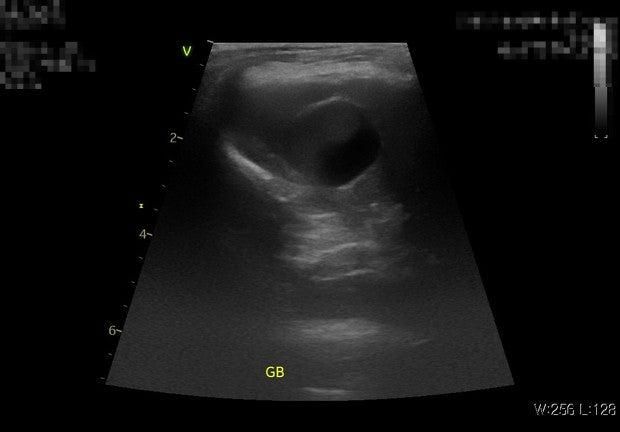

지금 초음파 그림 보면 담낭이 그렇게 커 보이지도 않고 담낭자백종과 같은 양상이 확인이 되지 않으니 우루사를 써 볼 수 있지만

담낭의 슬러지가 차는 경우는 부신피질기능 항진증과 같은 내분비계 질환에 의해서도 생길 수가 있으므로 내분비계 질환도 배제를 하셔야 될 것 같습니다